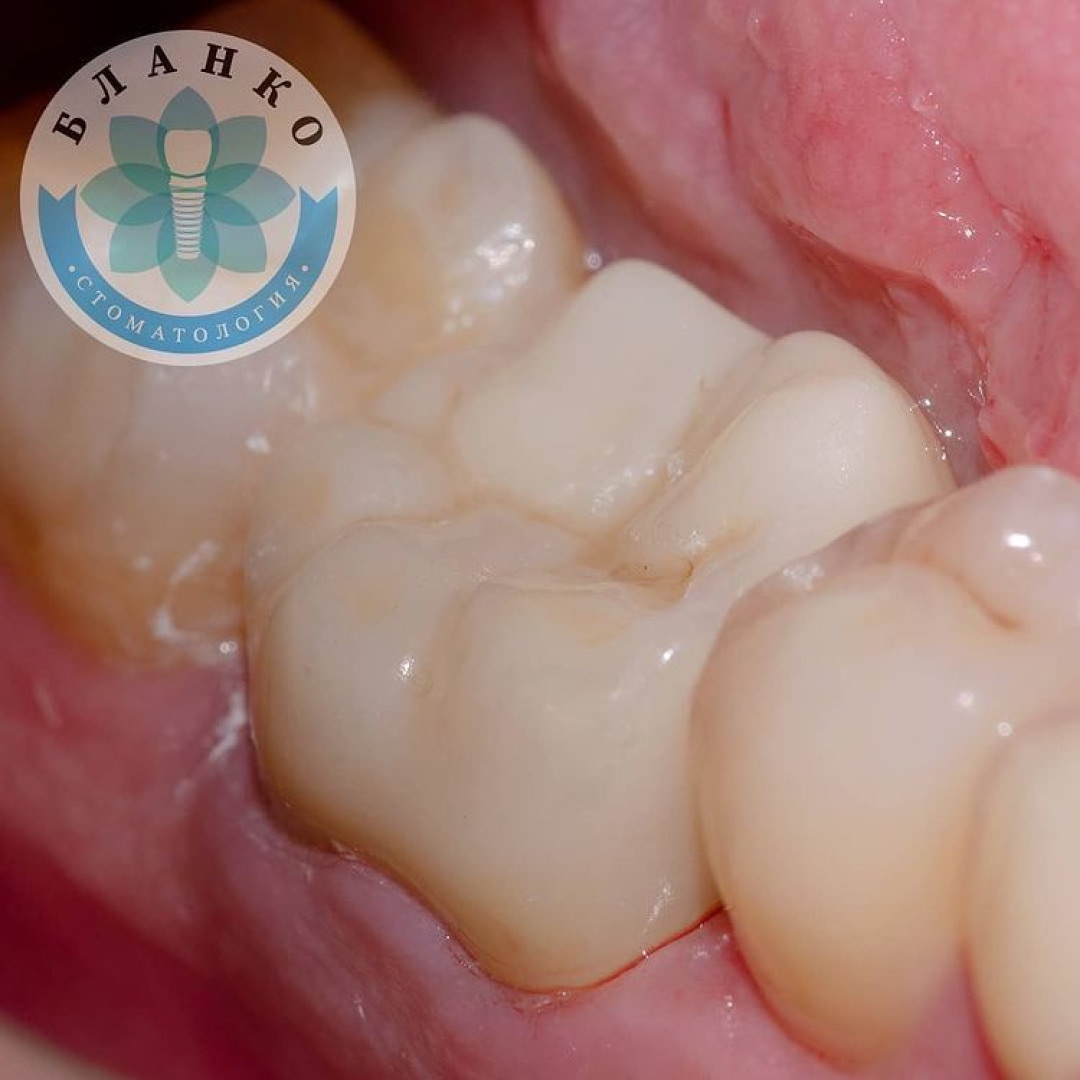

— сняты оттиски и изготовлена высокопрочная, гипоаллергенная и высокоэстетичная коронка из диоксида циркония.

✳️Итого, мы наблюдаем интересную ситуацию.

На примере этого клинического случая мы отчетливо видим, что экономить на своём здоровье нежелательно, потому что зуб — не туфель, в урну не выбросишь.